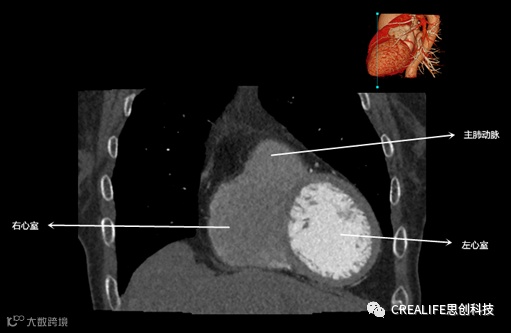

今天,跟大家分享心脏影像的经典层面——冠状位。通过冠状位的影像,我们可以从正位观察到心脏结构,看到主动脉的纵向剖面及冠窦交界处的心脏形态等多方位的心脏结构。现在,就让我们率先一睹“冠状位”的奇妙风采吧!

毋庸置疑,影像解剖学可为医师提供优良的诊断依据,包括瓣膜钙化程度、主动脉瓣环直径、主动脉窦直径及高度、冠状动脉开口高度、入径血管直径等关键数据,以此,为术前提供更全面的评估指标。